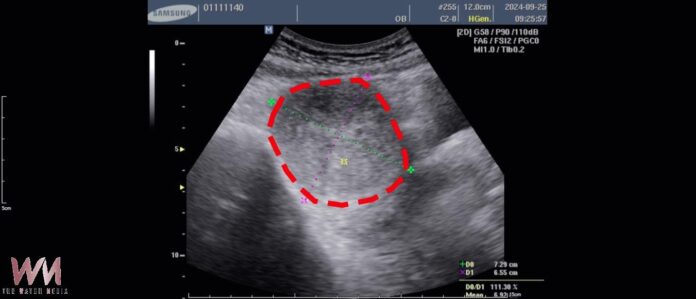

(觀傳媒中彰投新聞)【記者廖妙茜/台中報導】52歲的徐女士,長年飽受經痛、頻尿及下腹悶脹等症狀困擾。於113年9月20日至林新醫院健檢中心接受檢查時,經婦產科超音波檢查發現,其子宮前壁長有一顆約 7.3×6.5×6.2 公分、體積達 294 立方公分 的子宮肌瘤,大小約等同一顆中型芒果,且已壓迫膀胱,導致其日常需頻繁如廁、夜間多次起床影響睡眠,外出時亦須時時留意洗手間位置,生活品質明顯受到影響。

徐女士於113年10月7日完成手術,術後恢復狀況良好,僅住院兩日即順利出院。一個月後回診追蹤,超音波顯示肌瘤已縮小至3.7×3.6×2.9公分,體積僅剩38立方公分,約縮小近九成,大小相當於一顆小番茄。原本困擾多年的經痛及因肌瘤壓迫造成的頻尿、悶脹感,也明顯獲得改善。